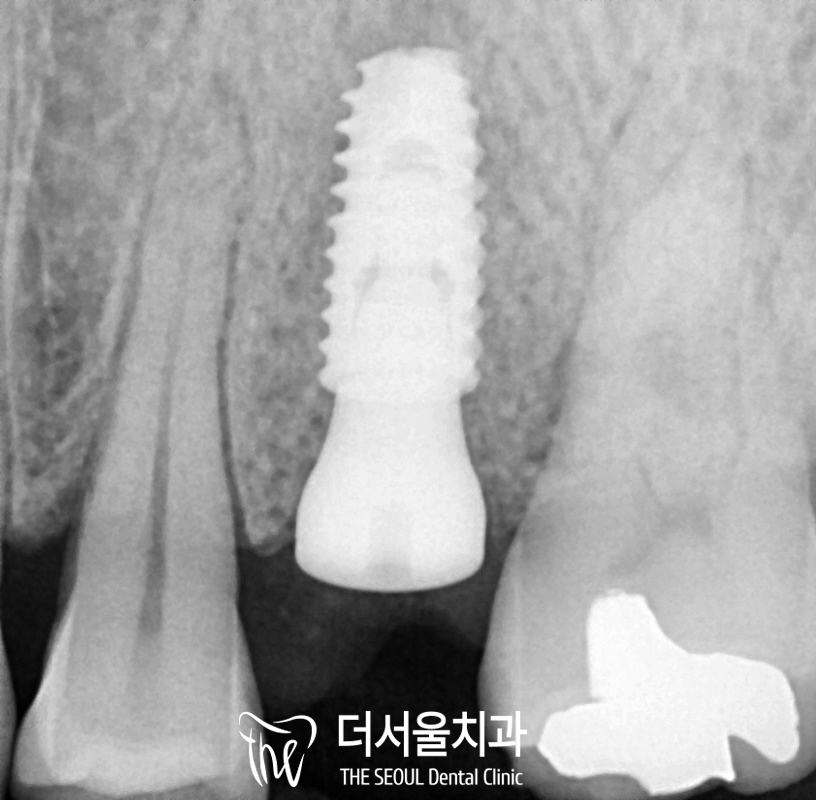

그리고 나면

크라운을 제작하여

연결해 드리는데,

여기서 중요한 한 가지가

더 있습니다.

더서울에서는

크라운에 홀을 두는 SCRP type

보철을 이용합니다.

이 환자의 경우

예전에 다른 곳에서 한(이제는 사라져버린..)

오른쪽 위 작은 어금니 임플란트는

방향도 조금 기울어져 있어서

지속적인 관리가 필요한데

심지어 보철에 홀이 없는 타입이라

a/s가 힘듭니다.

만약 문제가 생기면

크라운 전체를 뜯어내고

손을 봐야 된다는 뜻이죠.